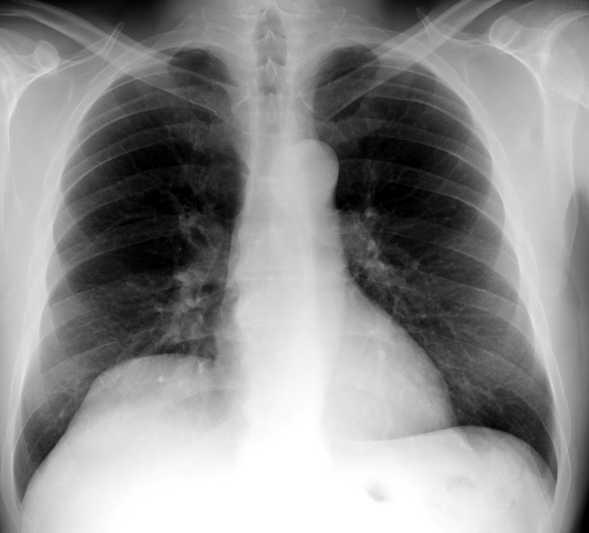

Tromboembolismo pulmonar Diafragma elevado 20%

Atelectasia crónica de LLI en paciente con enfermedad neuromuscular.